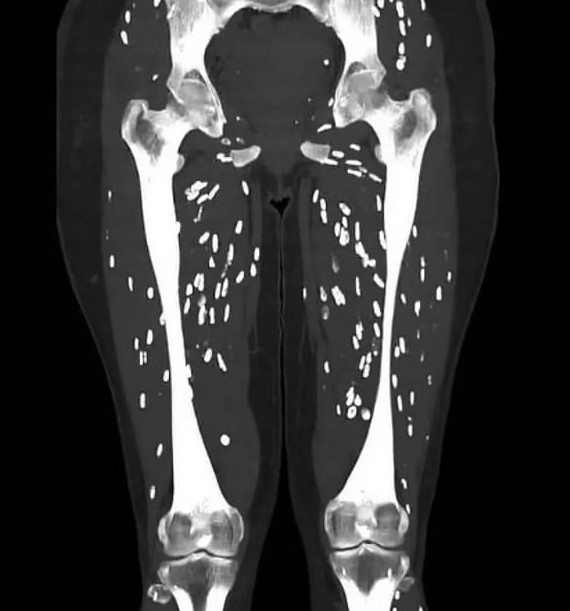

02/09/2024 13:27Sán làm tổ khắp bên trong người, tất cả do một kiểu nấu thịt lợn nhiều người Việt thường xuyên mắc phải

Tiến sĩ Sam Ghali, bác sĩ cấp cứu tại Đại học Florida (Mỹ) mới đây đã chia sẻ trường hợp nữ bệnh nhân mắc bệnh sán dây lợn. Bệnh này xuất hiện khi ấu trùng của loài sán dây xâm nhập vào các mô như cơ hoặc thậm chí là não. Thông qua việc chụp cắt lớp, có thể thấy chúng ký sinh trong cơ thể với hình dáng như những hạt gạo màu trắng.

Nguyên nhân ban đầu được xác định là bởi thói quen ăn xúc xích lợn chưa chín kỹ của người này.

Tiến sĩ Ghali cho biết, sán dây có thể gây bệnh và xâm nhập vào cơ thể của con người thông qua việc ăn trứng của chúng. Những quả trứng này có thể tùm thấy trong thịt lợn cũng như những chế phẩm từ thịt lợn chưa nấu chín, từ đó phát triển và gây bệnh trong cơ thể.